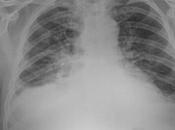

Existen atelectasias bibasáleses con derramé pleural asociado ia

PA DE TORAX (TELE DE TORAX) LA PROYECCION RADIOLOGICA OBTENIDA NOS MUESTRA LOS SIGUIENTES HALLAZGOS: -Tejidos blandos, simétricos, con adecuada densidad, sin... Leer el resto